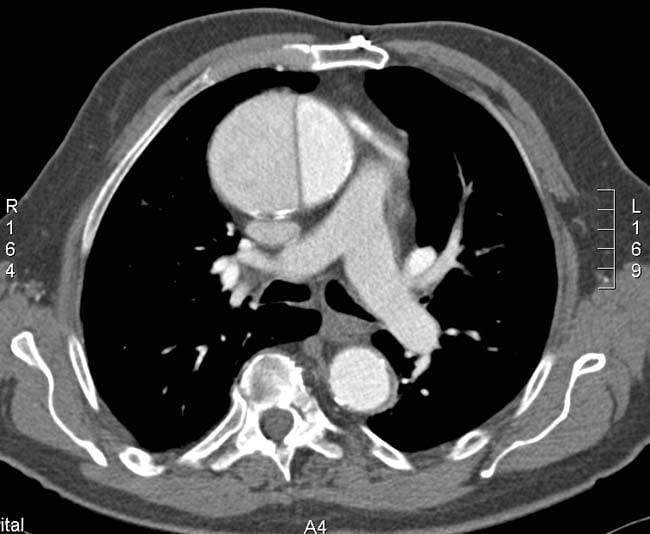

As with any disease entity, when considering our workup we need to evaluate our pretest probability to drive investigations and management. The current standard of care for AD workup is a CT scan of the chest and abdomen with contrast. A dissection protocol scan has a significant contrast and radiation load, so one must employ sound clinical judgment with his/her diagnostic decisions.

• As a refresher; recall that according to the Stanford Classification for aortic dissections, type A involve the ascending aorta, while type B dissections involve the descending aorta.